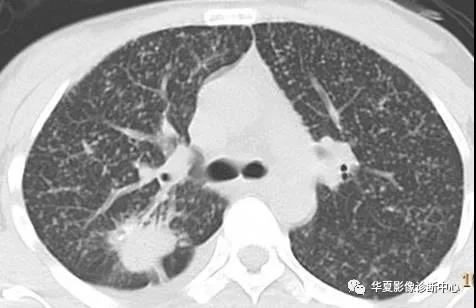

2.空洞或空泡样肺转移瘤:

原发灶多见于消化及呼吸系统,以鳞癌、腺癌、黑色素瘤、肉瘤、胚胎细胞瘤和移行细胞瘤多见,约占4%。转移性空洞形成机制可能与鳞癌中心角化物排空、腺癌黏液退变后黏液排空、肿瘤血供不足引起坏死、放化疗、肿瘤向支气管内侵犯形成活瓣等机制有关。

CT影像常多发,多为圆形,壁薄,光滑均匀,也可以表现为厚薄不一,肺门侧的壁较厚,外侧的壁薄,也可出现厚壁空洞,空洞壁常有明显强化。空洞性病变倾向于分布在胸膜下或叶间裂下,越靠近胸膜,空洞越小,直径较大的空洞多分布在肺的中带。厚壁空洞病变可随着病灶增大而出现分叶、毛刺及壁结节等恶性空洞的特点。

空洞性肺转移瘤变化快,短期内可见肿瘤增大、增多,有时可在治疗后自行消失。有学者认为空洞壁厚1-2mm及以下者不太符合缺血坏死所形成空洞的形态,因而称空泡更合适。空泡样转移瘤的瘤壁菲薄光滑,质均匀,可与肺纹理相连。